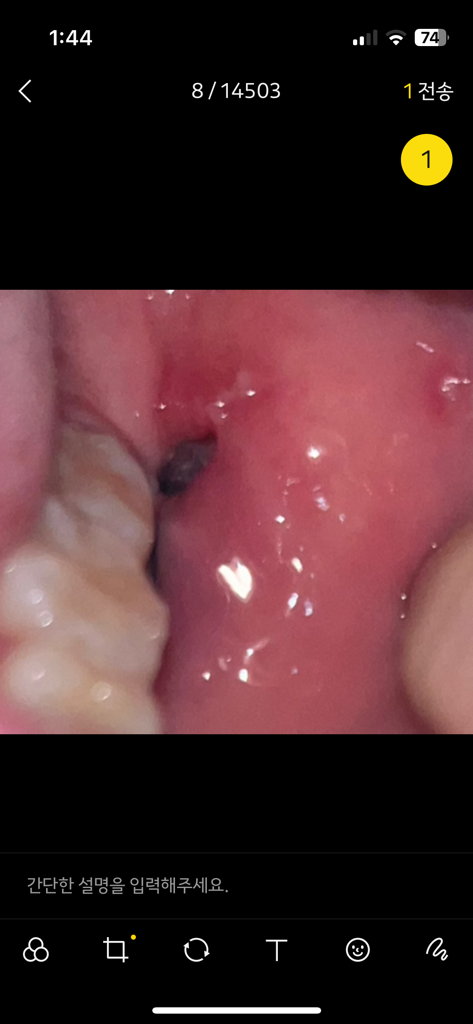

그런데 볼 안쪽에 웬 구멍이 나 있고, 그 밑으로 잇몸과 연결되는 부분까지 실밥으로 꿰매어져 있습니다.

이전에 작성했던 글에서 다른 치과의사 분께서 기구에 눌려서 난 구멍으로 보인다고 하셨는데, 기구에 눌렸다고 하기엔 마치 드릴로 뚫은 것마냥(?) 구멍이 크고 깊게 나있는데 무슨 구멍일까요...?

바로 윗부분은 마취주사를 맞아서 하얗게 헐어 있습니다.

아랫쪽 실밥으로 꿰매어져 있는 부분이 (사진상으로는 보이지 않음) 절개한 부분이라고 생각되는데, 혹시 실밥을 위쪽까지 덜 꿰매서 위쪽에 절개한 부분이 그대로 남아있는 것일까요...????? (구멍 뚫린 부분 바로 밑쪽에 실밥이 묶여 있어서 갑자기 그런 합리적 의심이 드네요)

매복사랑니발치를 하셧다면 잇몸절개를 넓게 하셧을꺼에요. 아마도 잇몸을 절개한 부분이 저렇게 보이는거 같습니다.

절개하여 발치를 하기 때문에 구멍이 나있는 것 처럼 보이는 것 같으며 자연히 아물게 됩니다.

사랑니를 발치하고 나면 발치를 한 부위에 공간이 생기거나 잇몸에 구멍이 난 것처럼 보일 수 있습니다.

잇몸은 보통 2주 정도 지나면 아물게 되며 잇몸 안쪽에 있는 치조골은 완전히 아무런데 3개월 정도가 걸리게 됩니다.